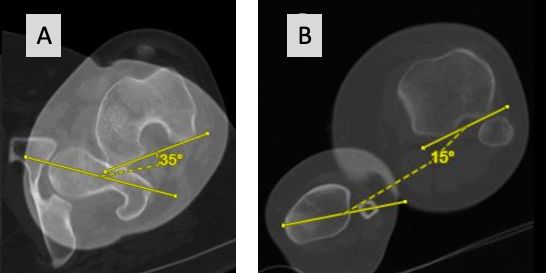

6. Basic biomechanics of tibia axial deformity and patella tracking

In the natural knee the TT is lateralized to the anatomical centre of the proximal tibia. The most common measurement of this ER positioning is the tibia-tubercle-trochlea groove (TT-TG) distance which on average is 7 mm and should be below 15 mm in normal knees [50]. This ER of the TT makes sense, since the natural knee has a screw home mechanism in full extension to lock the knee, which is driven by the medial condyle anatomy, menisci and both cruciate ligaments. After unlocking the knee during flexion, the tibia is internal rotating and beyond 60 ° of flexion the TT is under the trochlea of the femur with TT-TG 0 mm. In natural knees with patella dislocation, it could be shown that the TT-TG is significantly higher compared to normal knees [51]. During flexion the dynamic TT-TG is reduced, but never gets normal and in some patients, it is decompensating and gets even worse (Fig 20) [50]. This is the rational why in natural knees with pathological TT-TG more 15 mm, TT osteotomy with medialization is performed to bring the TT-TG back to normal and prevent patella maltracking or dislocation.

The complex screw home mechanism and self-rotational alignment of the natural knee during flexion cannot be reproduced with TKA implants. Only the bicruciate retaining/substituting and medial pivoting designs show some screw home mechanism whereas for all other TKA designs the TT-TG should be less than 5 mm in extension (tibia tubercle under the trochlea). This allows perfect patella tracking and brings the tibia component perpendicular to the TEA of the femur. In several biomechanical studies it could be shown that the rotational movements of all TKA designs during flexion are not natural, very variable and some of them even show paradoxical tibia external rotation [18]. Therefore, femorotibial mismatch in TKA between femur and tibia components during daily activities are common and remains a concern for bad function, early loosening and PE wear [16]. On the other hand, patellofemoral problems with maltracking and anterior knee pain are very common after TKA and the main cause is malrotation of the tibia and/or femur components [5, 10].